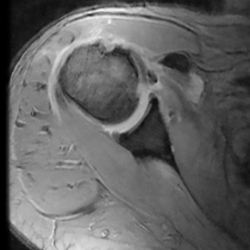

La radiografía en las proyecciones estándar ayuda a descartar otras patologías y en la visión de perfil de escápula se puede valorar la morfología de la apófisis coracoides y la distancia coracohumeral. La resonancia magnética nuclear (RMN) nos confirma el diagnóstico, el tipo de lesión, el grado de retracción y la degeneración grasa, la presencia o no de atrofia muscular e informa de otras patologías asociadas, como el impingement coracoideo y el estado del tendón de la PLB en los cortes axiales, y la afectación del resto del manguito rotador. Hay que tener en cuenta que la luxación de la PLB nos debe hacer sospechar una lesión del tendón subescapular(2,18).

Hay que tener en cuenta que la RMN estándar y la ecografía tienen falsos negativos en las lesiones parciales, siendo la artro-RMN mucho más sensible(19,20,21,22) (Figura 1).

Figura 1. Corte axial de una resonancia magnética nuclear donde se observa una luxación del tendón de la porción larga del bíceps.